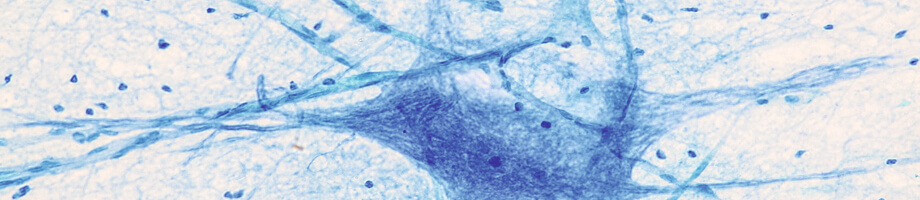

Een bekend voorbeeld van aspecifieke afweer zijn de fagocyten. Een fagocyt is een type witte bloedcel dat ziekteverwekkers opruimt door middel van fagocytose: ze omsluiten de ziekteverwekker en eten de indringer op.

Fagocyten hebben receptoren. Dat zijn eiwitten die vastzitten aan het oppervlak van een fagocyt. Door deze eiwitten kunnen zij de micro-organismen vinden om ze uiteindelijk onschadelijk te maken.

Er zijn verschillende soorten fagocyten: neutrofielen, monocyten, macrofagen, mestcellen en dendritische cellen. Al deze fagocyten zijn belangrijk voor onze aspecifieke afweer en het in stand houden van gezonde weefsels.